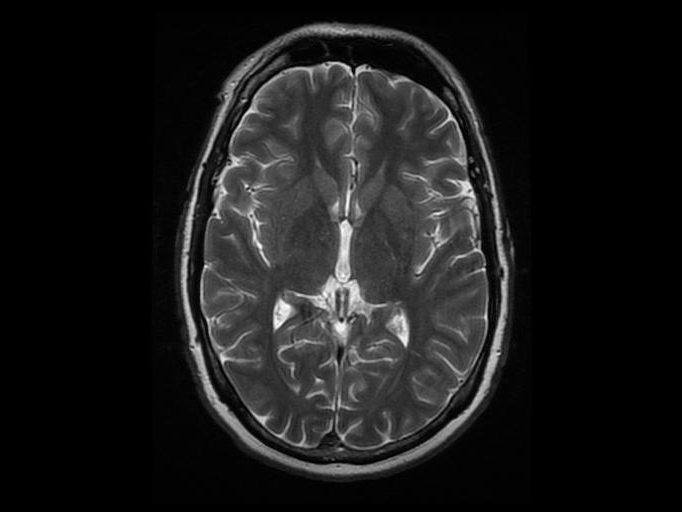

In a new study, MRI scans revealed that women's brains get re-wired during pregnancy. Jeffrey Hatcher via Flickr CC By 2.0